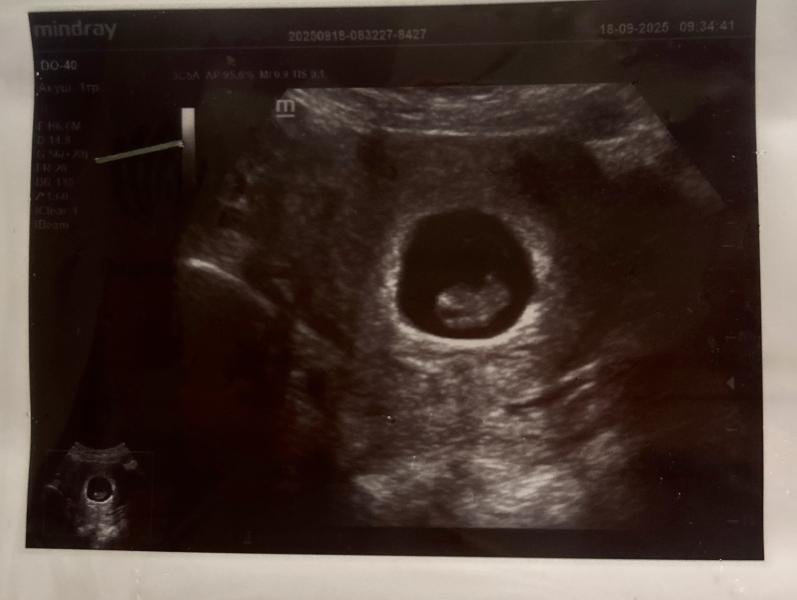

Человеку 8 недель🥹❤️

Решила сходить на УЗИ, потому что ранее делала только в 5.5 недель.

Заметно вырос, сердечко громко стучит❤️🔥

Меня переполняют чувства, впервые вижу здорового малыша за все свои беременности…